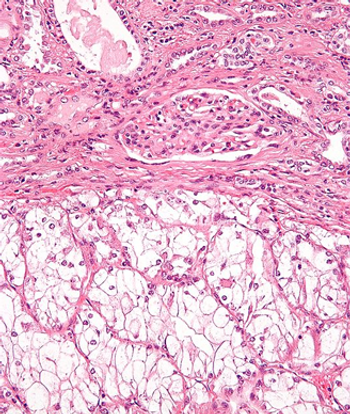

This slide show features various images of papillary, clear cell, chromophobe, and tubulocystic renal cell carcinoma.

A 38-year-old man presents with hematuria. A kidney mass is detected by imaging. Based on the shown biopsy, what is your diagnosis?

A 67-year-old man presents with hematuria and a kidney mass found on imaging. After further evaluation, a biopsy is performed. What is your diagnosis?

A full-term infant presents with abdominal distention and enlarged kidneys. After further evaluation, a biopsy is performed. What is your diagnosis?